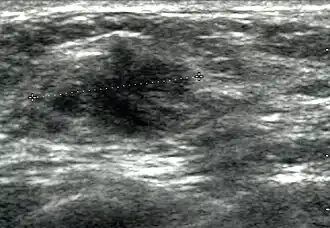

Breast ultrasound is a medical imaging technique that uses medical ultrasonography to perform imaging of the breast. It can be performed for either diagnostic or screening purposes[1] and can be used with or without a mammogram.[2] In particular, breast ultrasound may be useful for younger women who have denser fibrous breast tissue that may make mammograms more challenging to interpret.[3][4]

Elastography is a type of ultrasound examination that measures tissue stiffness and can be used to detect tumours.[7] Breast ultrasound is also used to perform fine-needle aspiration biopsy and ultrasound-guided fine-needle aspiration of breast abscesses.[8]

Breast ultrasound is typically performed using a frequency of 7 to 14 Megahertz, and may also include ultrasound of the axillary tail of the breast and axillae to detect abnormal nodes in the axilla, as lymphatic drainage of parts of the breast occurs through axillary lymph nodes.